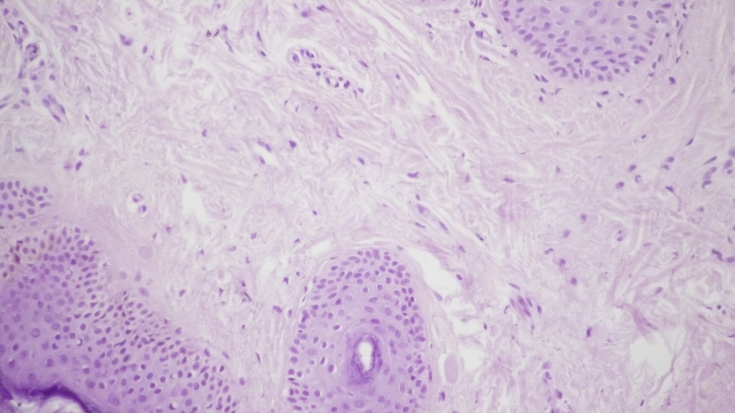

При контрольній гістологічній підготовці ділянки шкіри перед проведенням лікувальних заходів відзначалася вогнищева значно виражена запальна інфільтрація в дермі у вигляді вогнищевих скупчень лімфоцитів і гістіоцитів. (мал. 1а, b). Проліферація дрібних судин капілярного і синусоїдного типу супроводжувалася периваскулярною лімфоїдно-клітинною інфільтрацією (мал. 1c). Навколо окремих волосяних фолікулів і сальних залоз запальна інфільтрація стимулювала проліферацію фібробластів і розвиток склеротичних процесів. (мал. 1d).

Мал. 1. Морфологічна картина шкіри перед лікувальними заходами: вогнищева запальна інфільтрація дерми, х200; запальна інфільтрація навколо волосяних фолікулів, ознаки фіброзу, х200; проліферація дрібних судин капілярного типу з периваскулярної лімфоїдно-клітинною інфільтрацією, х200; сальні залози з вогнищевою запальною інфільтрацією в прилягаючій дермі, х200.